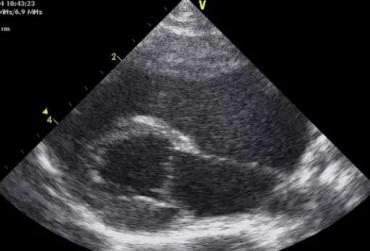

Zwężenie zastawki trójdzielnej jest jedną z form dysplazji pojawiającą się w różnym stopniu nasilenia (najczęściej łącznie z niedomykalnością zastawki) zarówno u psów, jak i u kotów. Cechami charakterystycznymi definiującymi zwężenie zastawki trójdzielnej są: obecność rozkurczowego wybrzuszenia (doming) płatków zastawki, zmniejszona ruchomość płatków, zmniejszona średnica ujścia zastawki. Mimo że zmiany morfologiczne aparatu trójdzielnego są typowe w przebiegu TVD i są znakiem rozpoznawczym tej choroby, nie są one zawsze bardzo silnie wyrażone i nie zawsze można mieć bezsprzeczną pewność diagnostyczną, bazując na badaniu echokardiograficznym [10]. Przypadki takie zdarzają się przede wszystkim u pacjentów, u których nie postawiono diagnozy we wczesnym etapie życia, a którzy pojawiają się na badaniu dopiero w starszym wieku z zaawansowanymi zmianami i niejednokrotnie z klinicznymi objawami prawostronnej niewydolności mięśnia sercowego i towarzyszącymi zaburzeniami w rytmie. W takich przypadkach obraz choroby może przypominać arytmogenną kardiomiopatię prawokomorową (arrhythmogenic right ventricular cardiomyopathy – ARVC) [1, 8]. Preekscytacja jest często obserwowana u ludzi z anomalią Ebsteina. U zwierzat, podobnie jak u ludzi, obecność dodatkowej drogi przewodzenia może nigdy nie prowadzić do rozwoju tachykardii nadkomorowej lub arytmia ta pojawiać się może dopiero w późniejszym okresie życia. Opisany przypadek jest przykładem pacjenta z dysplazją zastawki trójdzielnej i prawostronną niewydolnością serca będącą najprawdopodobniej konsekwencją tachykardii nadkomorowej.